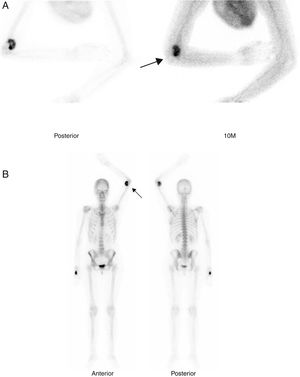

Mujer de 36 años, en seguimiento por tumoración dolorosa y progresiva en cara antero-medial del codo izquierdo e impotencia funcional, de 2 meses de evolución, resistente al tratamiento analgésico. Refería antecedente traumático previo, siendo diagnosticada de rotura fibrilar muscular. Ante la persistencia del cuadro, se realizó RMN ambulatoria, que sospechó un sarcoma de partes blandas, ingresándose para estudio de extensión. Los estudios de laboratorio y TC toraco-abdominal fueron negativos. Mediante gammagrafía ósea en 2 fases (figs. 1A y B), se demostró un área de captación heterogénea en región anterior del codo izquierdo, sin hallazgos significativos a otros niveles. Se planteó diagnóstico diferencial entre sarcoma de partes blandas, condrosarcoma y osteocondroma con degeneración maligna. Finalmente, se decidió biopsia percutánea eco-guiada, cuyo resultado fue de tumoración mesenquimal sin caracteres de malignidad, estableciéndose el diagnóstico definitivo de miositis osificante. Se recomendó reposo, tratamiento antiinflamatorio y rehabilitación posterior. A los 3 meses, presentó mejoría clínica con disminución del dolor, flexión completa y extensión a 120°. El control por radiología simple (figs. 2A y B) y TC sin contraste (fig. 3) reveló una masa calcificada, compatible con el diagnóstico anatomo-patológico.

Gammagrafía ósea en 2 fases tras la inyección de 814 MBq de 99mTc-hidroxi-difosfonato. Imágenes estáticas a los 10min (fase tisular [A]) y cuerpo completo a las 2h (fase ósea [B]), en las que se observa captación heterogénea del radiotrazador en región anterior del codo izquierdo (flechas).